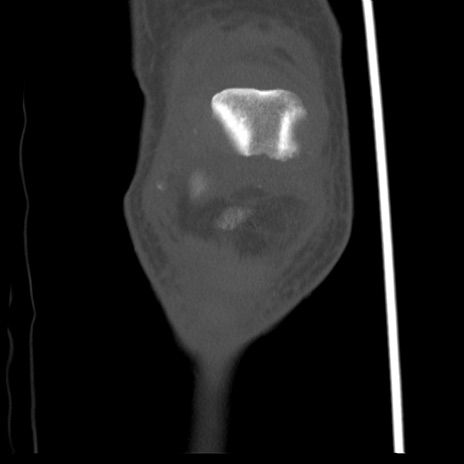

右膝関節CT

横断像